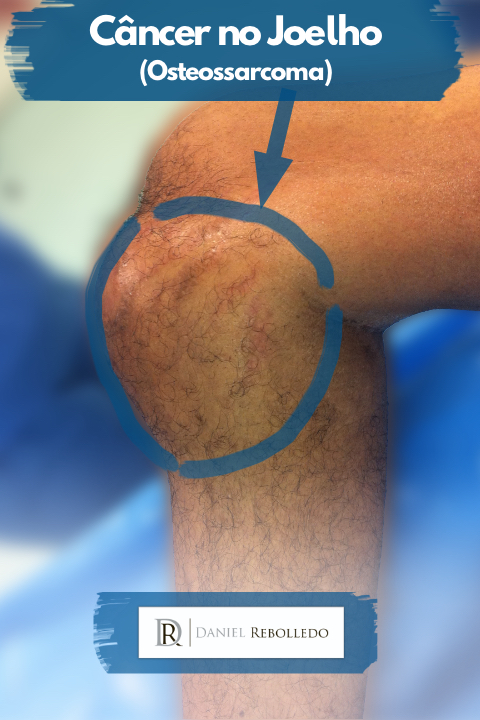

- Osteossarcoma.

O principal câncer no joelho infantil é o osteossarcoma.

Este é o principal tipo de sarcoma ósseo em crianças e adolescentes e seu principal local de aparecimento é justamente o joelho.

Câncer no joelho fotos